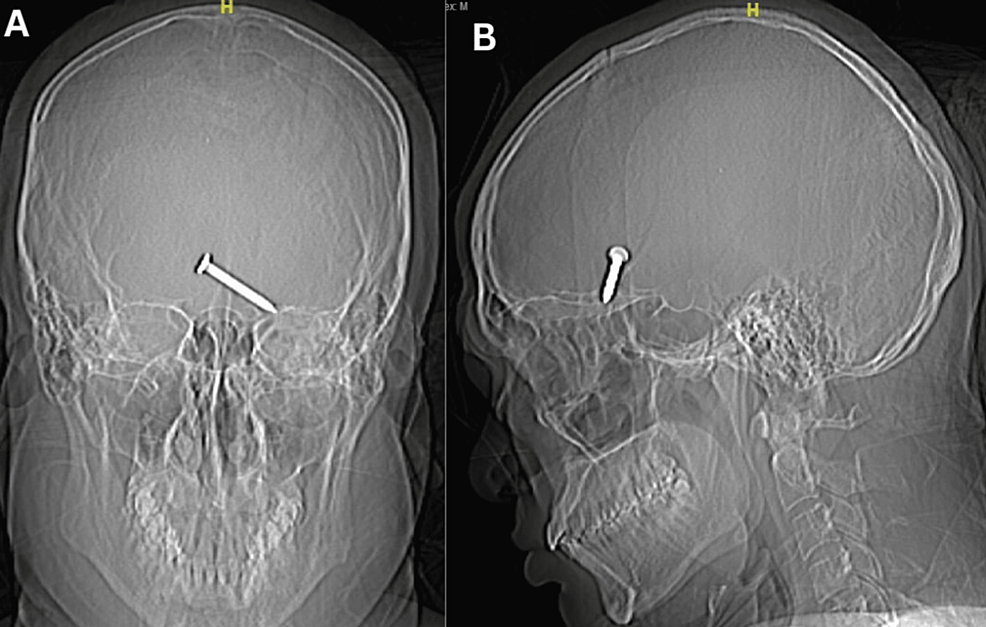

Bajo ese contexto, la herramienta dejó de funcionar y el hombre, cuya identidad no ha sido revelada, dio vuelta la pistola para ver cuál era el problema, pero se disparó accidentalmente y el clavo se enterró en su ojo.

Si bien el individuo estaba sin lentes de seguridad, el elemento no alcanzó a dañar el globo ocular, ya que entró por un costado del ojo. No obstante, llegó hasta el lóbulo frontal de su cerebro.

El hombre fue trasladado hasta el hospital Sultanah Bahiyah en Alor Setar, en Malasia, donde presentó una hemorragia interna en su cerebro, motivo por el cual se sometió a una cirugía para remover el clavo, logrando sobrevivir a pesar de las lesiones.